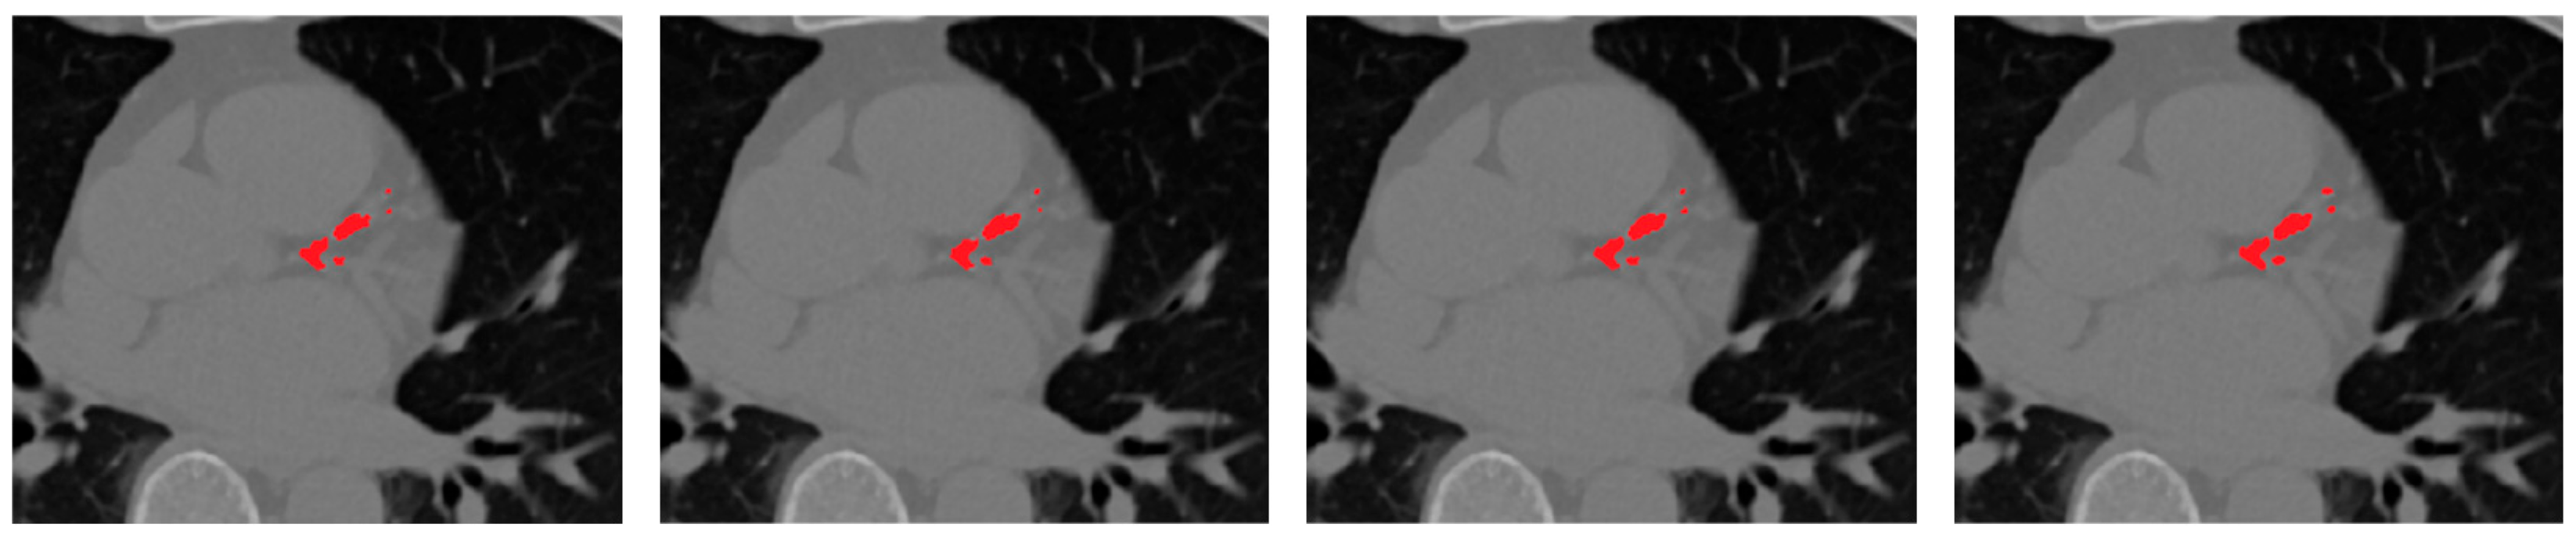

Figure 7 presents representative qualitative comparisons, illustrating that the selective fusion generates cleaner, anatomically coherent segmentation masks, effectively preserving true calcifications while suppressing spurious predictions. The proposed selective fusion produces more anatomically consistent calcification masks with reduced false positives and improved boundary continuity.

Figure 7. Comparison of fusion strategies for ensemble CAC segmentation. From left to right: rank-based selective ensemble output, soft-voting ensemble.